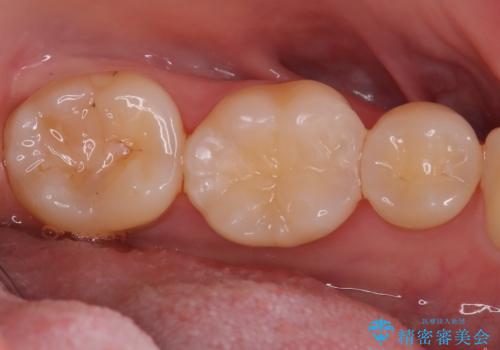

- 「前歯の歯の色が気になる」を主訴に来院された患者さんです。歯の大部分がプラスチックの材料で治療されていました。そこが劣化し変色していたためオールセラミッククラウンで治療を行いました。前歯の色を全体的に白くするために当院でオフィスホワイトニングも行いました。

左上2番の大部分がプラスチックの材料で治療されていました。そのプラスチックの材料が劣化して変色し虫歯になっている状態でした。なので古いプラスチックの材料を全て除去し、その下の虫歯を取った後、オールセラミッククラウンで治療を行いました。オールセラミッククラウンを装着する前に当院にてホワイトニングを行いました。